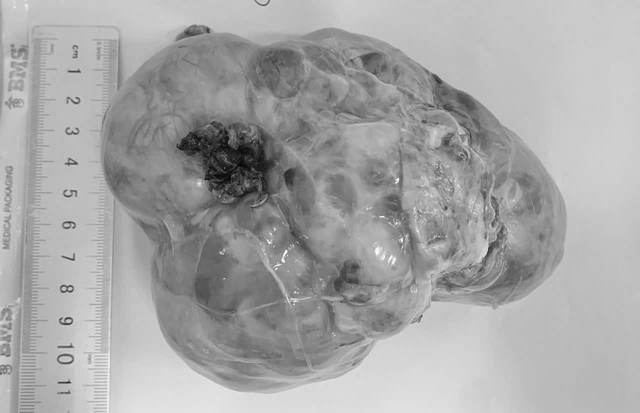

Khối u ổ bụng được phát hiện khi đã phát triển lớn ở bệnh nhi

ẢNH: Đ.X

Theo các bác sĩ, điểm chung đáng lo ngại là 3 trường hợp đều được phát hiện khi khối u đã phát triển lớn, gây chèn ép các cơ quan trong ổ bụng, khiến việc phẫu thuật trở nên phức tạp, đồng thời làm tăng nguy cơ phải điều trị phối hợp nhiều phương pháp sau mổ.